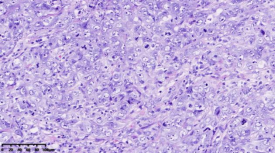

在本项研究中����,研究人员利用基本的组织形态学方法及免疫组织化学法对TNBC进行分型��:腔面雄激素受体型(LAR)(图1A)��,免疫调节型(IM)(图1B)�����,基底样免疫抑制型(BLIS)(图1C)���,间充质型(MES)(图1D)�����。评价各亚型临床病理参数(如发病年龄��、肿物大小���、淋巴结转移等)���,组织形态学(肿物中央瘢痕形成���、浸润模式����、肿瘤间质浸润淋巴细胞���、细胞排列方式���、细胞核形态��、核分裂计数���、间叶化生等)以及免疫表型(p53����、Rb���、PD-L1���、MMR等)�����,结果显示���:1.TNBC分型的临床病理����、组织形态学和免疫表型特征不尽相同���,有望成为复杂的基因表达谱分析的替代选择����,为TNBC的分型治疗及靶向治疗提供理论依据��;2.生物标记物 PD-L1作为重要的生物学指标�����,对个体化治疗及免疫治疗有重要的临床指导价值��;3.乳腺癌中dMMR作为一个低频发生事件��,不太可能作为免疫治疗有效性的评估手段����。该成果发表在Virchows Archiv期刊����,题目为“Subclassifying Triple-Negative Breast Cancers and Its Potential Clinical Utility”��。文章DOI为����:10.1007/s00428-022-03329-0�����。

图1. 基于组织形态学及免疫组织化学标记物的TNBC分型